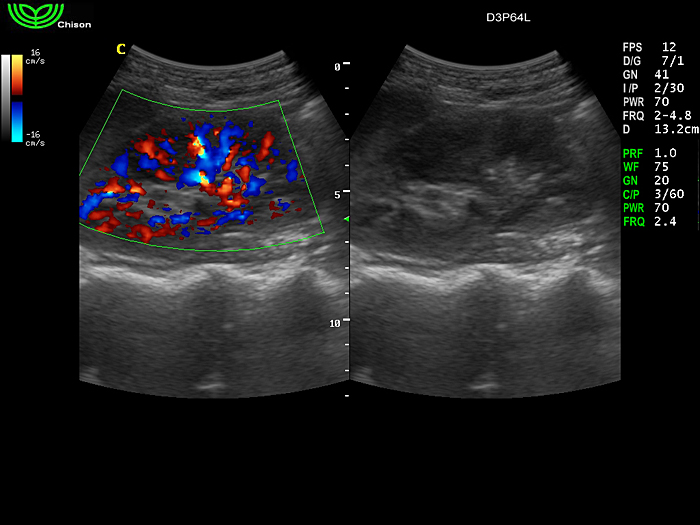

D3P64L 3.0МГц, фазированная решетка.

2.0МГц – 4.4МГц. Применения: кардиология, брюшная полость, акушерство. |